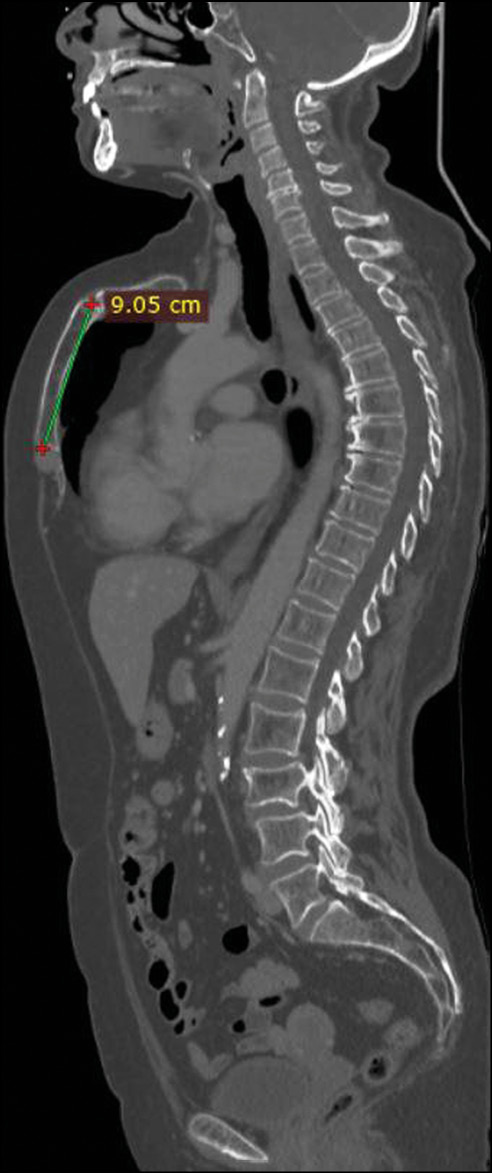

She underwent CT of the chest and abdomen with contrast enhancement, which showed the absence of metastatic lesions and any other respiratory tract disorders but revealed a chondromanubrial deformity with a dorsal-open angle of 130° and a sternum body length of 9 cm, which was not depressed in the lower third. Dorsal kyphosis was also present.

Fig 2. Sagittal whole body computed tomography scan showing a sternum body length of 9 cm and dorsal kyphosis.